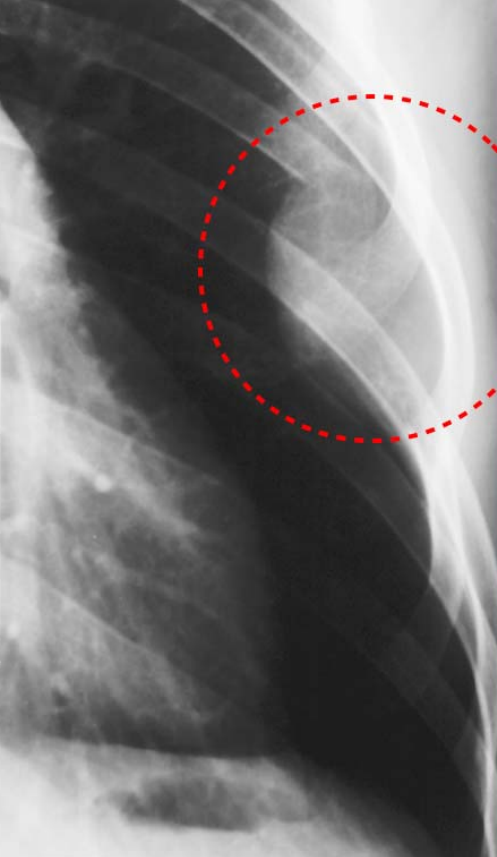

Figure1